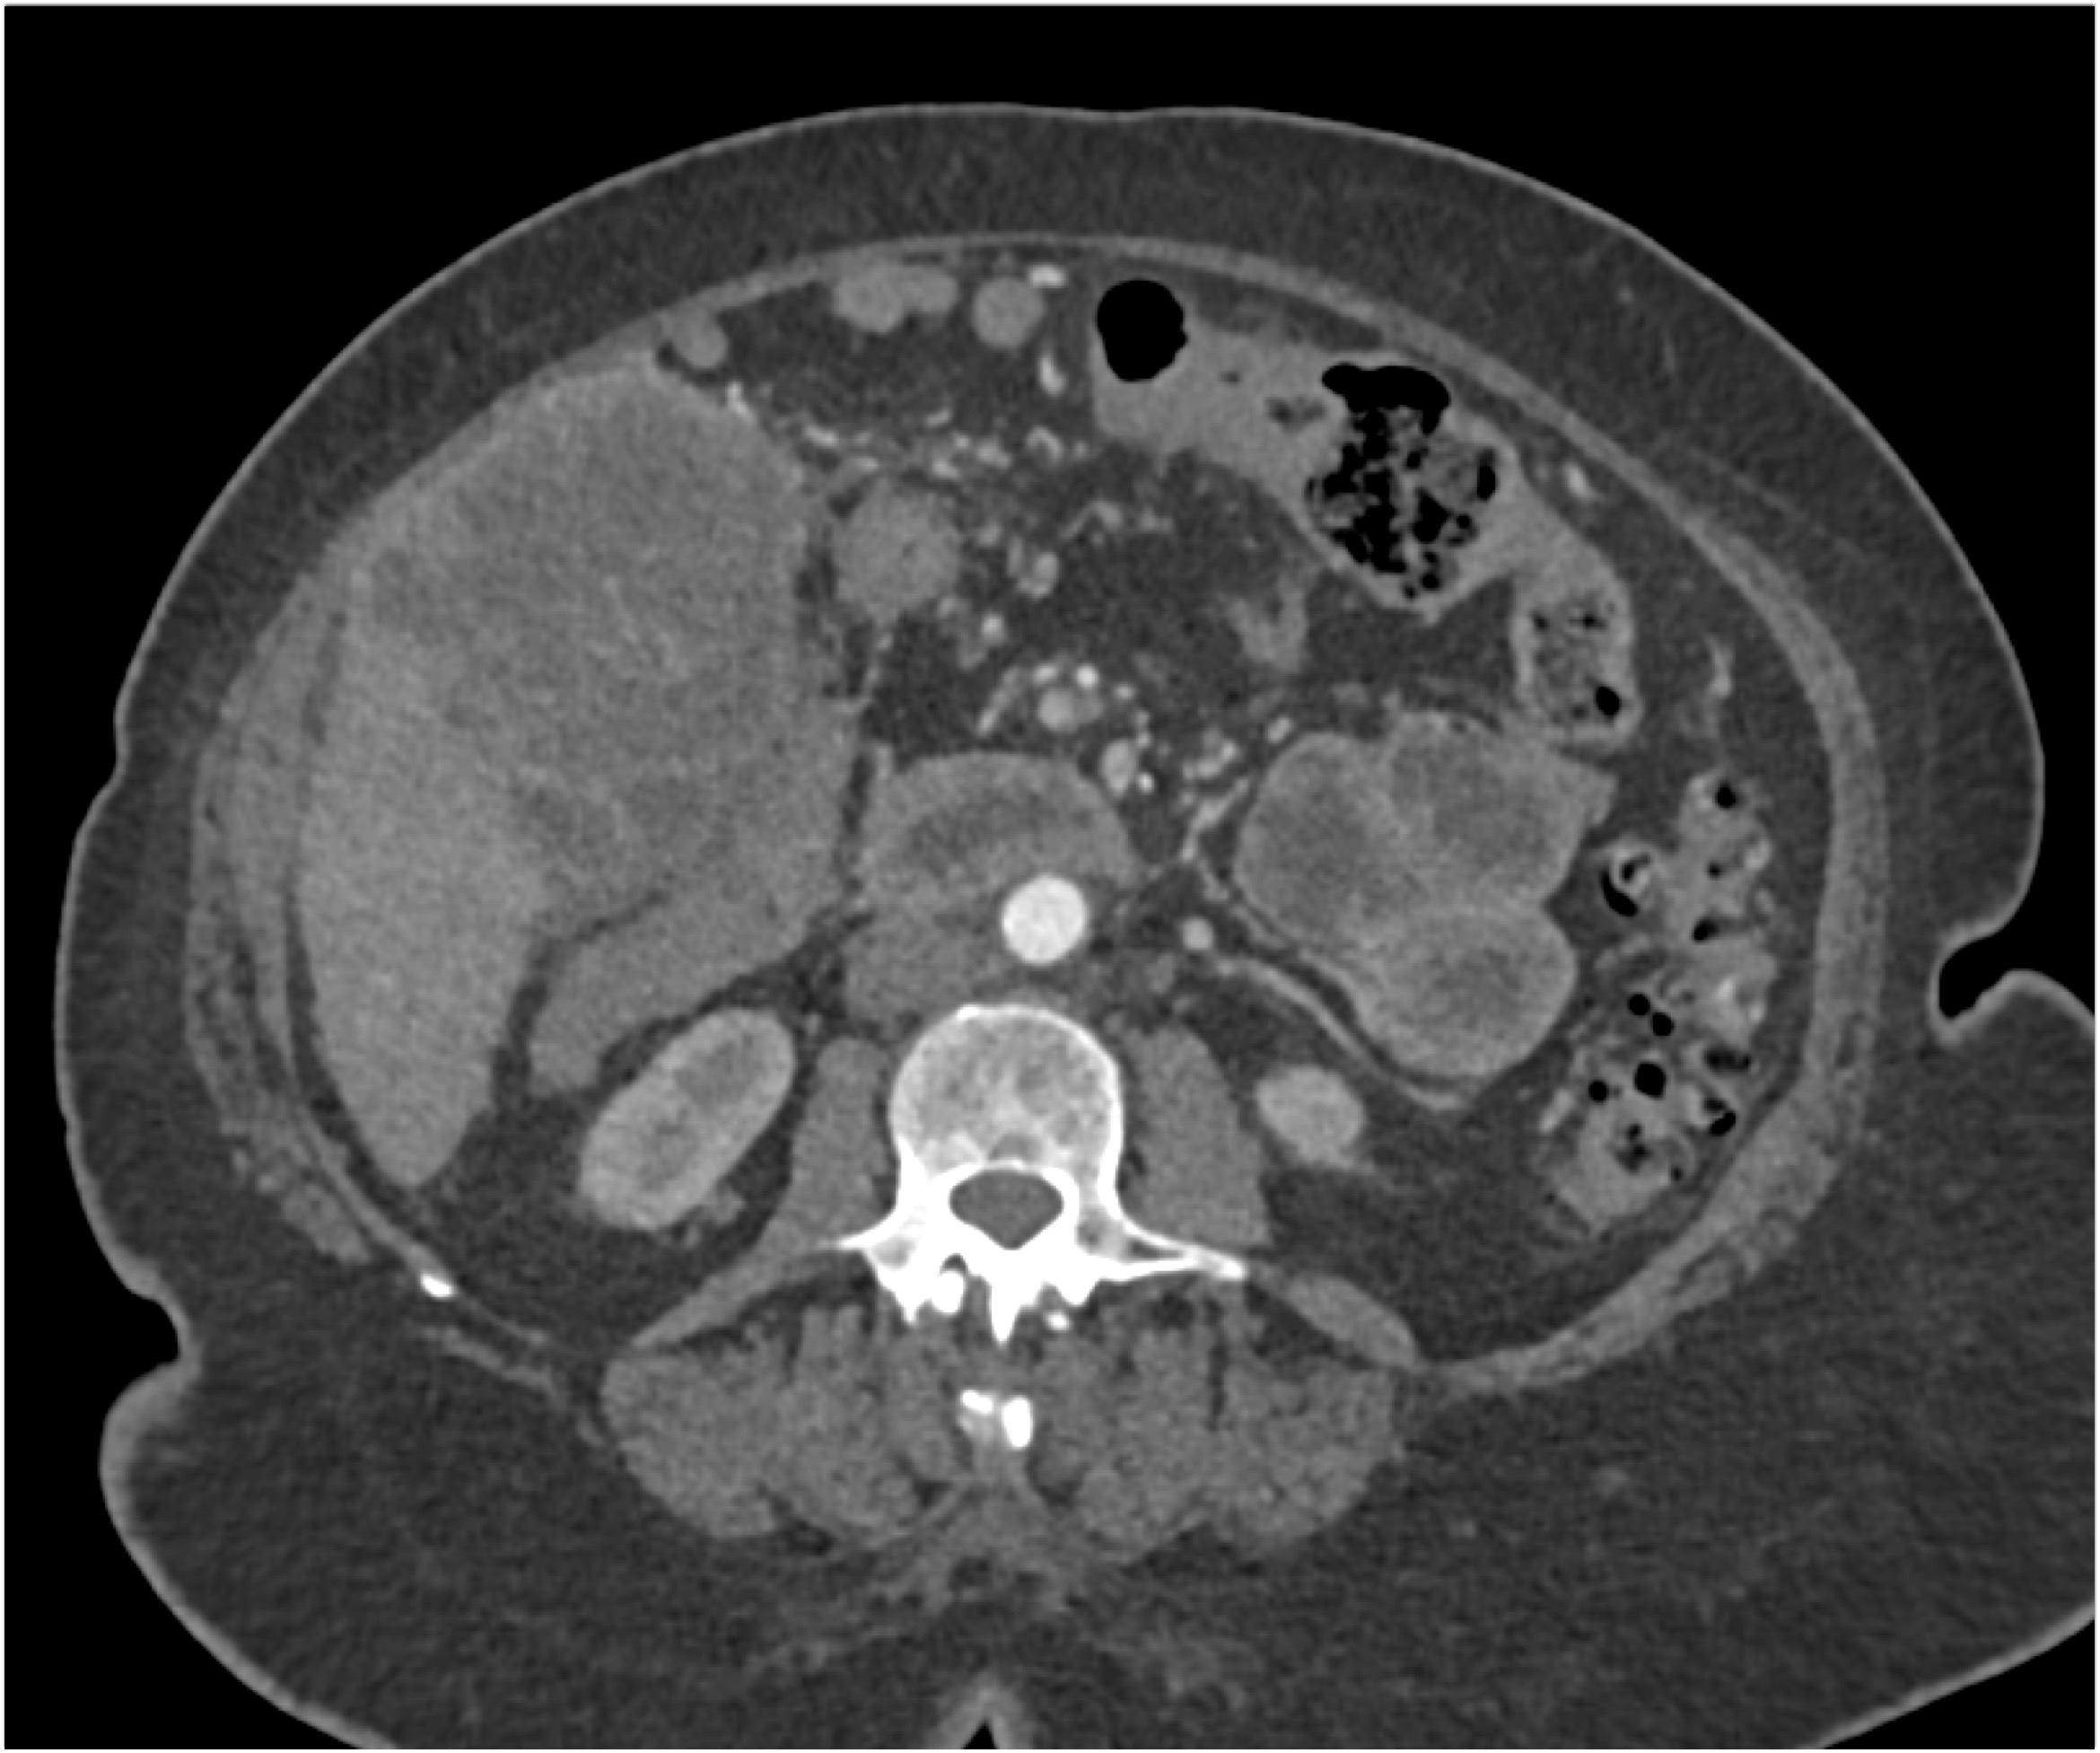

The most likely diagnosis in this case is?

hepatoma

cholangiocarcinoma

gallbladder cancer

hepatic adenoma